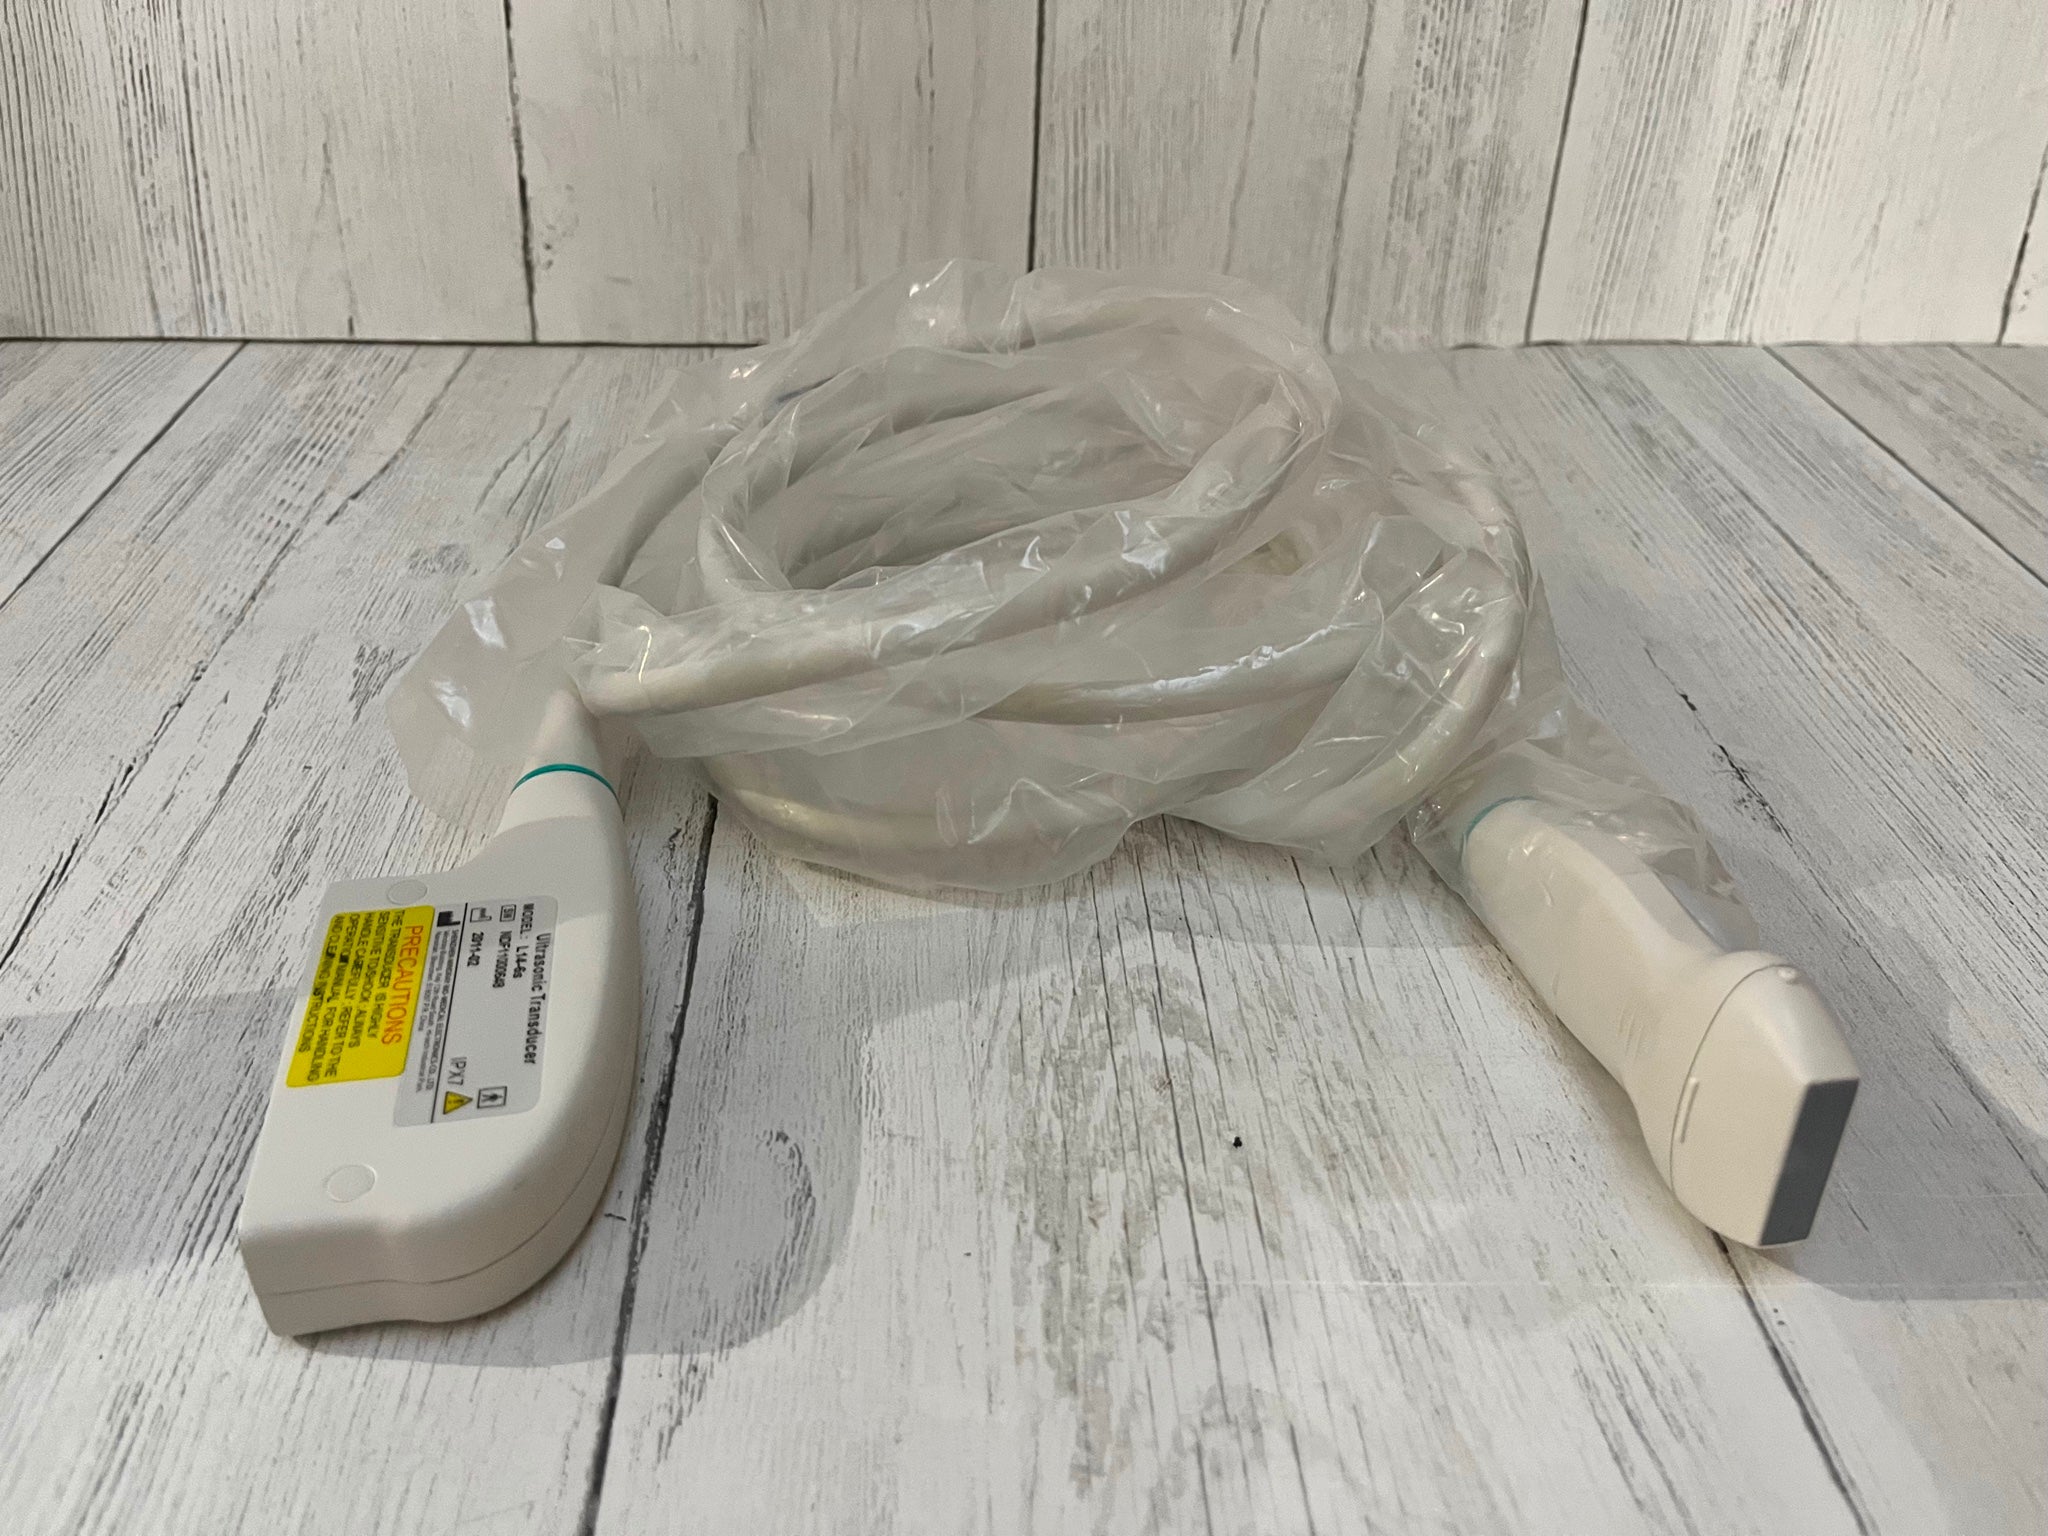

- Convex Probe: 3.5MHz-5MHz

- Depth:90mm-305mm

- Dimension: 156x60x20mm

- Weight: 270g